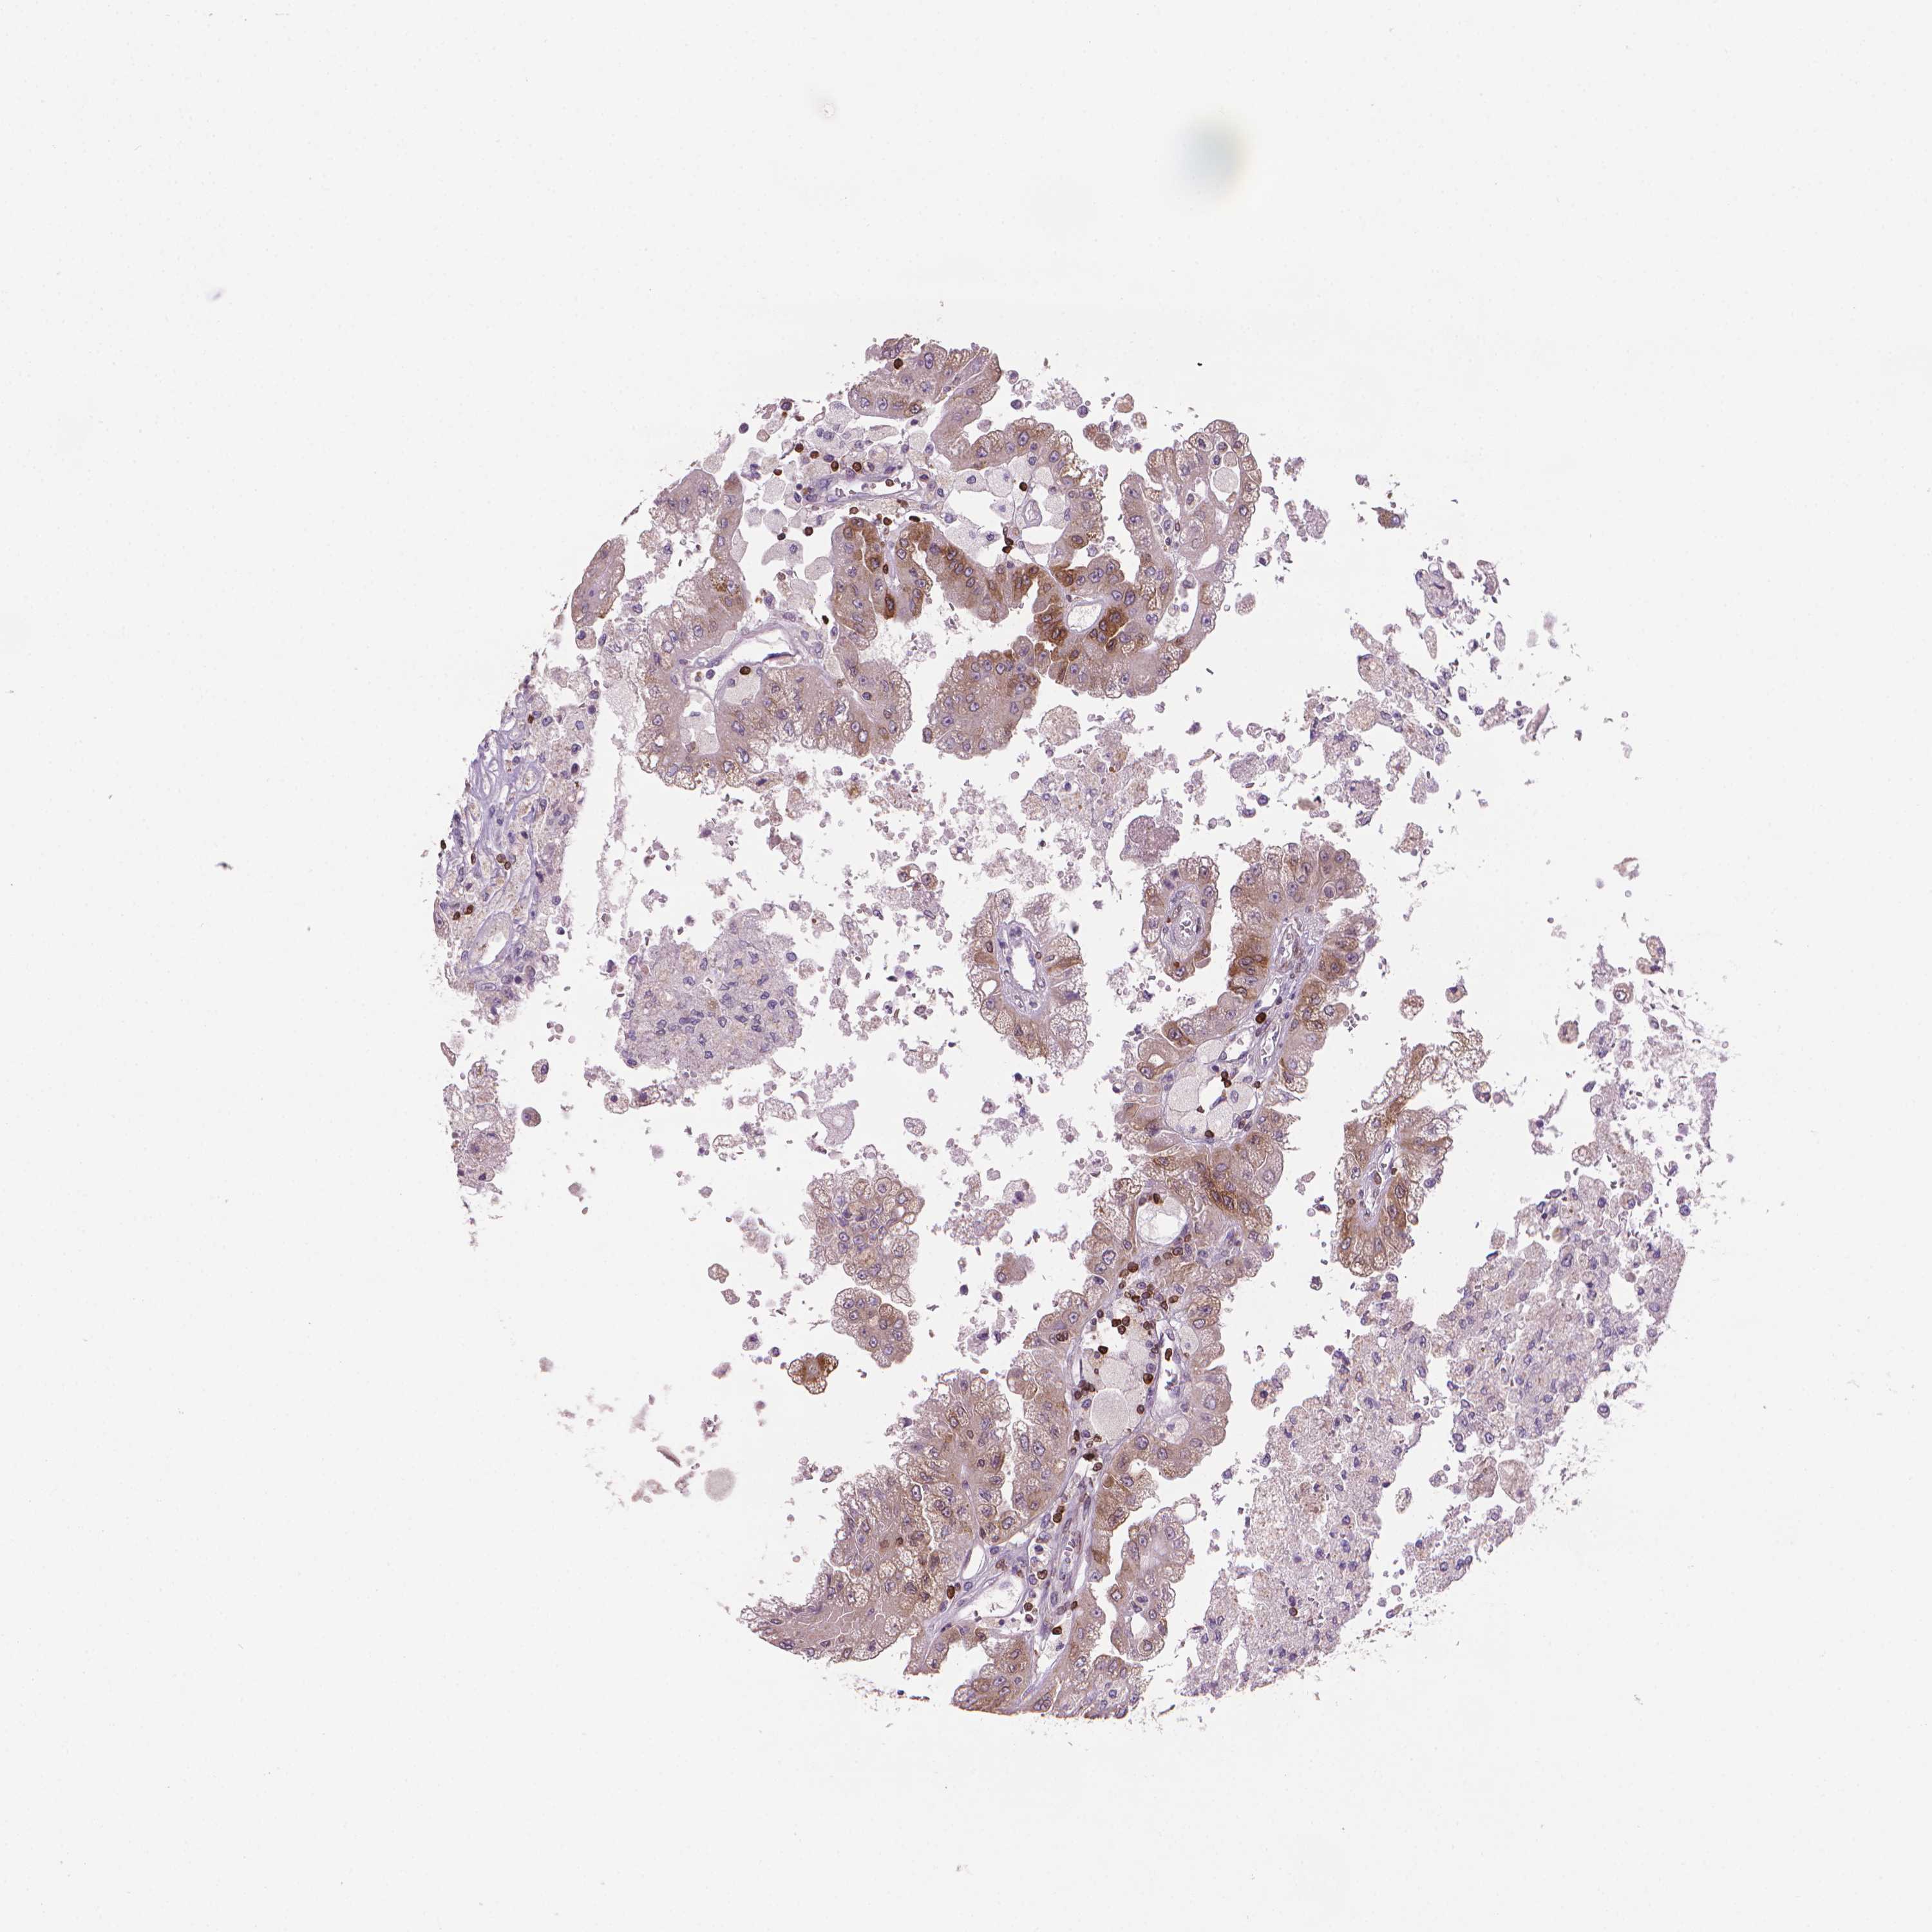

Kidney renal papillary cell carcinoma

KIDNEY RENAL PAPILLARY CELL CARCINOMA (TCGA) - Interactive survival scatter ploti

The Survival Scatter plot shows the clinical status (i.e. dead or alive) for all individuals in the patient cohort, based on the same data that underlies the corresponding Kaplan-Meier plots. Patients that are alive at last time for follow-up are shown in blue and patients who have died during the study are shown in red.

The x-axis shows the expression levels (FPKM) of the investigated gene in the tumor tissue at the time of diagnosis. The y-axis shows the follow-up time after diagnosis (years). Both axes are complimented with kernel density curves demonstrating the data density over the axes. The top density plot shows the expression levels (FPKM) distribution among dead (red) and alive patients (blue). The right density plot shows the data density of the survived years of dead patients with high and low expression levels respectively, stratified using the cutoff indicated by the vertical dashed line through the Survival Scatter plot. This cutoff is automatically defined based on the FPKM cutoff that minimizes the p-score. The cutoff can be changed by dragging the vertical line or by entering a cutoff value in the square labeled "Current cut-off".

Under the Survival Scatter plot the p-score landscape (black curve; left axis) is shown together with dead median separation (red curve; right axis). Dead median separation is the difference in median mRNA expression between patients who have died with high and low expression, respectively. It is calculated as follows: median FPKM expression of dead patients with high expression - median FPKM expression of dead patients with low expression. This is intended to aid the user in visually exploring custom cutoffs and the associated p-scores and dead median separation.

Individual patient data is displayed and can be filtered by clicking on one or more of the category buttons on the top of the page. Categories describing expression level and patient information include: high, low, alive, dead, female, male and tumor stages. The scale of the x-axis can be toggled between linear and log-scale by clicking on the "x log" button. Mouse-over function shows TCGA ID, patient information and mRNA expression (FPKM) for each patient.

& Survival analysisi

Kaplan-Meier plots summarize results from analysis of correlation between mRNA expression level and patient survival. Patients were divided based on level of expression into one of the two groups "low" (under cut off) or "high" (over cut off). X-axis shows time for survival (years) and y-axis shows the probability of survival, where 1.0 corresponds to 100 percent.

BCL2 is not prognostic in Kidney Renal Papillary Cell Carcinoma (TCGA)